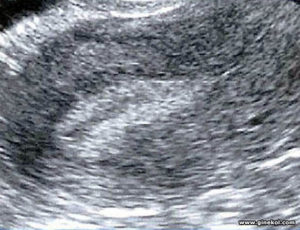

- То, как выглядит эндометрий на УЗИ, зависит от уровня концентрации в плазме крови эстрогенов и прогестерона. К тому же ультрасонографические особенности строения слизистой оболочки матки имеют прямую зависимость от фазы менструального цикла. В дни менструаций в проекции маточной полости регистрируют только тонкую и прерывистую линию гиперэхогенного характера.

- В пролиферативной фазе переднезадний размер слизистой матки утолщается до 3,5 мм, а эхоструктура становится изоэхогенной и более однородной. В данном случае такие УЗИ-признаки, как некоторое снижение эхогенности и повышенная однородность говорят о бурном развитии желез, которые также меняют и свое расположение. После произошедшей овуляции эндометрий матки на УЗИ приобретает более высокую эхогенность благодаря скоплению большого количества секрета в расширенных протоках желез.

- На протяжении периовуляторного периода ткань всего эндометрия несколько гипоэхогенна. Данный признак служит достоверным критерием, который отражает произошедшую овуляцию. Однако при проведении трансвагинальной эхографии такое состояние эндометрия встречается до и после овуляции. На протяжении секреторной фазы толщина эндометрия достигает своего максимума, что равняется 6-12 мм. При этом в лютеиновую фазу эхогенность также повышена, что объясняется изменением железистого компонента и отеком стромы эндометрия.

Для того чтобы понимать, на какой день цикла назначить исследование, следует знать, когда и какая патология визуализируется лучше всего. Обычно увидеть самую четкую и достоверную картину можно на 7-10-й день менструального цикла.